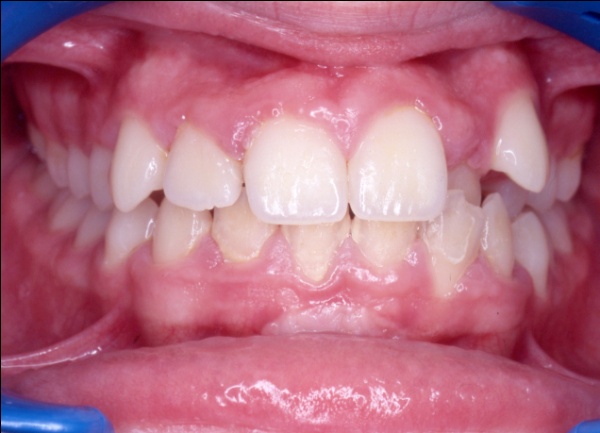

Ce cas illustre parfaitement que l’orthodontie ne peut pas se résumer à un simple alignement des dents. Ici, l’exclusion de la canine supérieure gauche (23) pouvait faire croire à un manque de place dû à un excès de volume dentaire. En réalité, un diagnostic précis a révélé deux causes : une endomaxillie (palais trop étroit) et une avancée anormale de l’hémiarcade gauche, qui empiétait sur l’espace de la canine. Le traitement a consisté à élargir le maxillaire par disjonction, puis à réaligner les dents sans extraction, en restaurant l’harmonie occlusale.

1 - Arcades avant/après

Le traitement a été conservateur, sans extraction, grâce à une thérapeutique de gain d’espace adaptée. L’arcade a retrouvé sa largeur, son équilibre et son esthétique, par la restitution d’une architecture osseuse et dentaire cohérente. L’occlusion est désormais fonctionnelle, stable et conforme aux rapports naturels entre les deux arcades.